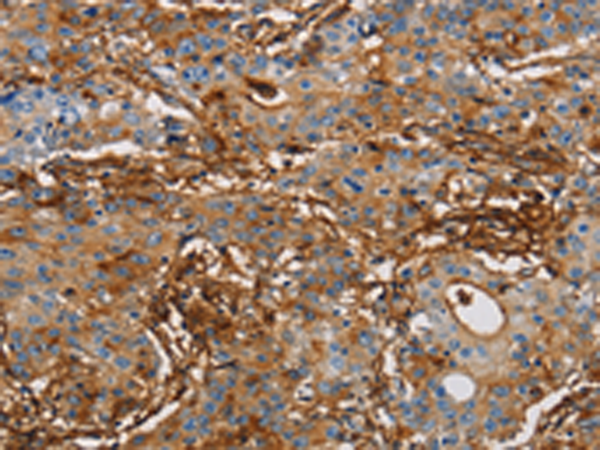

分类: 科研抗体货号: P07991别名: BB2; CD54; P3.58应用: WB,IHC反应种属: Human